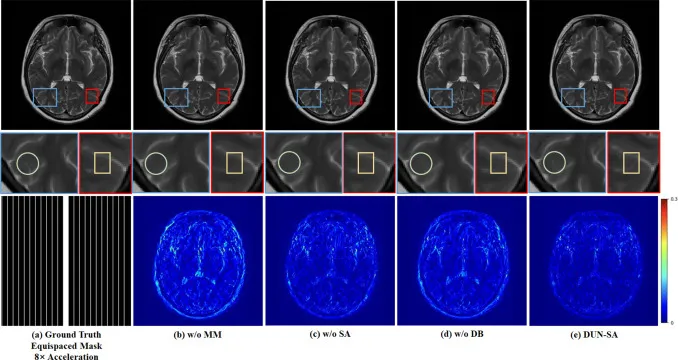

本节首先比较了DUN-SA与其他方法在训练过程中的收敛性能,结果显示DUN-SA在整个训练过程中始终保持更高的PSNR和SSIM值以及更低的MAE,证明其收敛性能更优。其次,研究了DUN-SA在不同程度模态间错位下的性能表现,发现随着错位程度增加,DUN-SA的性能下降速度慢于SAN,表明其对空间错位具有更强的鲁棒性。在空间配准性能比较中,DUN-SA不仅实现了全局对齐,还保留了局部结构,优于传统方法和SAN,尤其是在高加速因子下,SAN逐渐无法有效对齐,而DUN-SA受影响最小。此外,实验评估了DUN-SA在参考数据不完善场景下的适应性,即使参考模态欠采样,DUN-SA也表现出优越性能,并始终优于其他多模态重建方法,验证了其对参考数据质量变化的适应性。消融研究表明,最优迭代次数为12,并且每个关键组件(多模态辅助、空间配准、去噪块)对于提升重建性能都是必要的。模型验证通过可视化中间结果,直观地展示了空间配准任务和重建任务之间的相互促进作用,提升了网络的透明度。最后,对模型复杂度进行分析,指出DUN-SA虽然复杂度居中,但考虑到其综合重建性能,具有良好的性价比。

图13. 在fastMRI数据集上,8倍加速和1D等距欠采样掩模下,各组件效果的视觉比较。第一行:不同方法重建的图像;第二行:感兴趣区域的放大视图;第三行:8倍加速的等距掩模和不同方法的误差图。